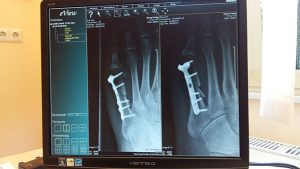

Doctor holding X-ray